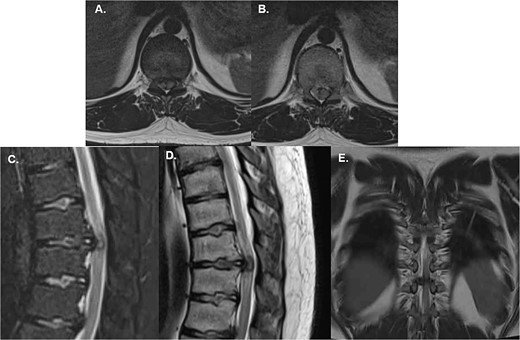

A 27-year-old male mechanic with no significant medical history presented to the emergency department after an acute event of dorsal pain and bilateral lower limb weakness. The patient reported lifting a heavy piece of equipment, when he experienced a sudden, sharp pain in the mid-back, followed immediately by a loss of strength in both legs. The weakness caused him to collapse to the ground, and he was unable to stand or walk thereafter. Upon arrival at the emergency department, the patient was alert and hemodynamically stable but exhibited profound motor deficits in the lower extremities. The relevant findings to the physical exam included motor function assessment showing 1/5 strength bilaterally in the lower limbs with sensory function intact across all dermatomes (Supplementary Video 1). The patient was unable to void spontaneously, and a Foley catheter was placed to relieve urinary retention. However, he did present with a certain degree of sacral preserving, accounting for spontaneous erections and preserved defecation. An urgent MRI of the thoracic spine revealed a large, extruded disc herniation at T9/T10, causing severe compression of the spinal canal. The spinal cord appears flattened at the level of herniation, with significant associated edema. No evidence of calcification or chronic changes was noted, suggesting an acute pathology (Fig. 1).

Emergency MRI of the patient shows (A) and (B) axial T2W projections that demonstrate a severe compression of the spinal cord given the central location of the extruded disc, (C) a sagittal T2W with fat suppression allows to see the extruded disc nucleus of the T10-T11 disc causing compression of the spinal cord; edematous changes are also visible, (D) shows a T1W sagittal midline image of the extruded disc which also shows a flattened spinal cord with associated edema; note the absence of any calcification or changes associated with chronic progression and (E) is a coronal T2W image of the disc herniation showing its central location with a slight predominance over the right canal.